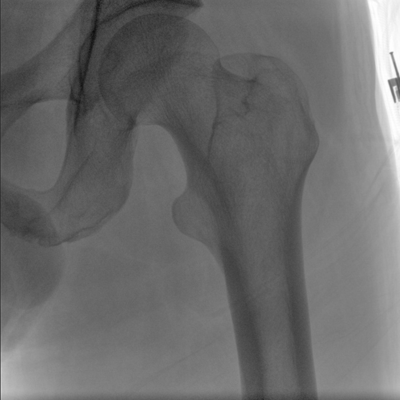

臨床適用科室:骨科、普通外科、矯形外科、創(chuàng)傷外科、泌尿外科、脊柱外科、疼痛外科、消化科、婦科等科室。

大尺寸動態(tài)平板探測器,高DQE、低噪聲、圖像清晰。采用多分辨率圖像增強(qiáng)處理技術(shù),不同部位不同圖像處理算法,滿足客戶多樣化的需求。